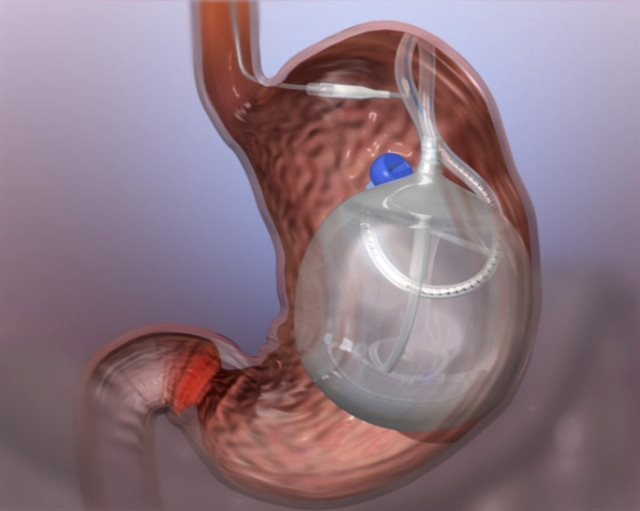

La técnica del balón intragástrico consiste en una esfera de látex llena de suero fisiológico colocado vía endoscópica en el estómago bajo sedación en un ingreso ambulatorio. Su principal efecto es la disminución de la motilidad del estómago reduciendo el tiempo de vaciado tras la ingesta de alimentos y provocando, en la mayoría de los casos, una sensación de saciedad temprana y demorada durante las comidas.